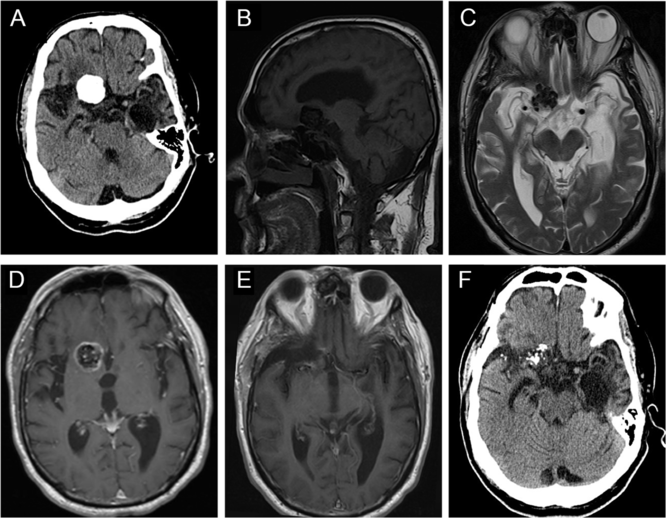

A 70-year-old man was referred to neurosurgery clinic with 4 years of progressive headache, gait difficulty with falls, confusion, and mood changes. His past medical history was significant for medication-controlled seizures secondary to remote encephalitis caused by West Niles virus, hypertension, and obstructive sleep apnea. His physical examination revealed no focal neurological deficits except a short stride length in his gait. He scored 23/30 on the Montreal Cognitive Assessment.Reference Nasreddine, Phillips and Bédirian12

CT of the head revealed a well-circumscribed heavily calcified mass, measuring 2.4 × 2.6 × 1.8 cm, centered within the right basal frontal lobe, with moderate perilesional vasogenic edema (Figure 3A). On MRI, this mass was hypointense on both T1WI and T2WI, with patchy central T2 hyperintensity, and peripheral enhancement (Figure 3B–D), with no evidence of a dural tail. The lesion was in close proximity to the right internal carotid artery (ICA), proximal middle cerebral artery (MCA), and anterior cerebral artery (ACA) (Figure 3D). It was also mildly displacing the prechiasmic segment of the right optic nerve (Figure 3C). There was encephalomalacia within the anterior left temporal lobe with associated ex vacuo dilatation of the temporal horn, which may be a consequence of his previous encephalitis (Figure 3A and C).

Figure 3: Imaging of a right basal frontal calcifying pseudoneoplasm of the neuraxis. (A) Preoperative axial computed tomography (CT) revealed a 2.4 × 2.6 × 1.8 cm well-circumscribed, lobulated, densely calcified lesion centered within the anterior skull base, with some perilesional vasogenic edema. (B) This lesion was hypointense on sagittal T1WI. (C) Axial T2WI demonstrated that the lesion was hypointense with patchy central hyperintensity, and causing some displacement of right optic nerve. (D) The mass demonstrated peripheral contrast enhancement and was in close proximity to the right anterior cerebral artery. (E) Postoperative magnetic resonance imaging showed near-total resection of the lesion. (F) Follow-up CT scan showed no progression of the residual disease after 7 years.

Postoperative Course

Postoperative imaging confirmed a near-total resection of this right basal frontal CAPNON (Figure 3E). On postoperative examination, the patient’s headache improved, and he did not sustain any new focal neurological deficits. However, he continued to have progressive global neurological decline including gait difficulty and cognitive decline and required a nursing home placement 6 months after the surgical intervention. It is possible that he had an undiagnosed neurodegenerative condition. He remained stable without focal neurological deficits or radiographic evidence of disease progression 7 years later (Figure 3F) when he underwent a head CT due to a ground-level fall.